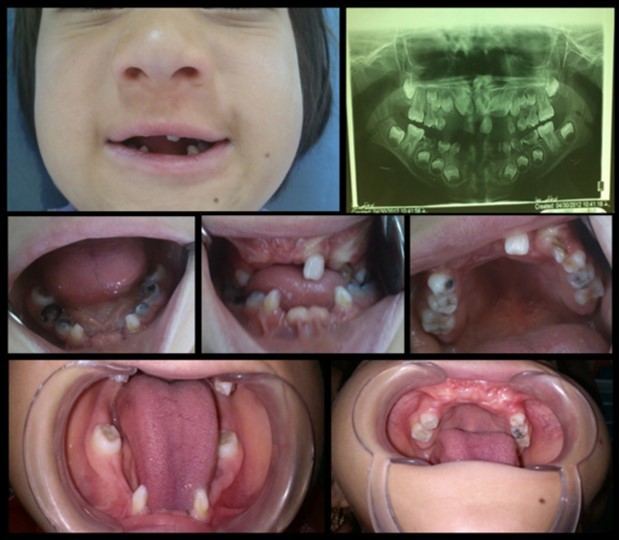

Oral Findings:

The mandibular and maxillary incisors were absent (excluding upper left lateral maxillary incisor which was loose) mandibular deciduous molars, right maxillary first deciduous molar and left deciduous maxillary canine had severe decay and the right maxillary permanent canines were erupting. Multiple frenulum and attaching labial mucosa to alveolar mucosa were also observed (Figure 2).

In Radiographic examination of tooth, maxillary incisor tooth germs were absent and all of the four “second permanent molars” were un-erupted and root of primary mandibular canines have severe mesial curve (Figure 2).

Figure 2.Intra oral photographs and panoramic radiograph: anodontia of mandibular and maxillary incisors, absence of mucobuccal fold in maxillary and mandibular anterior region, congenital absence of the incisors, conical shaped teeth and multiple frenula.